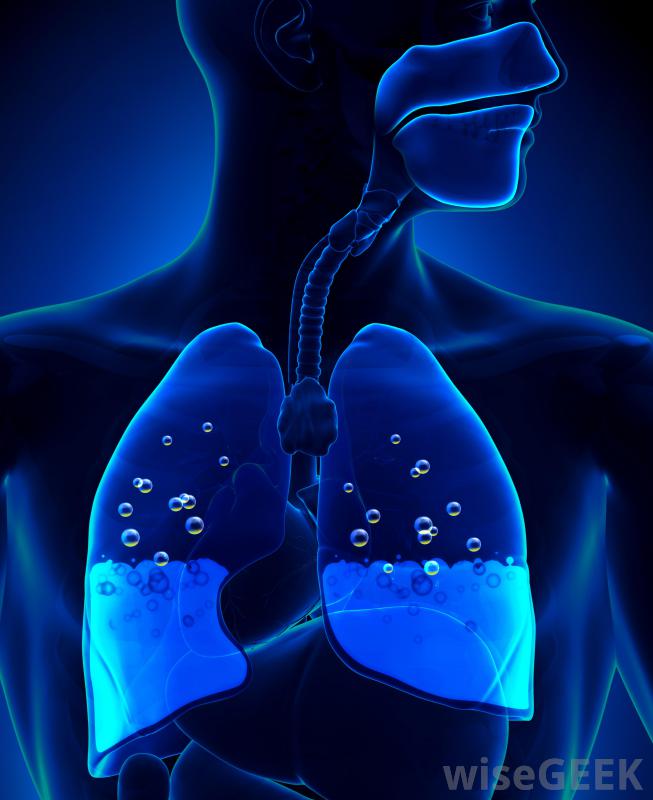

胸腔积液是胸腔内多余液体的积聚,胸腔包围着肺部。正常情况下,胸膜中含有一层薄薄的液体,以保持肺部在呼吸过程中的平稳运动。当有过多液体时,右侧胸腔积液发生在右侧胸膜中,右侧胸腔积液比左侧胸腔积液更容易导致充血性心力衰竭胸腔积液。右侧胸腔积液或右侧胸腔积液的发生,是一种潜在疾病的结果。右侧和左侧胸腔的液位通常不同,称为非对称性胸腔积液。胸腔积液也可孤立于其中一个空洞,称为单侧胸腔积液。右胸腔积液主要与充血性心力衰竭(CHF)有关胸腔积液是胸腔积液在肺部周围胸腔中的积聚。胸腔积液的最初症状通常是当胸腔中的液体达到一定量时大约500毫升。报告的症状包括呼吸困难或疼痛,以及呼吸时胸壁的运动减弱。当胸部和背部被交叉或轻拍时,共振也会减少当用听诊器检查时,呼吸音可能会很迟钝,也可能会有不寻常的声音,如噼啪声或摩擦声,这是由于过多的液体产生的摩擦造成的。如果怀疑这些症状,通常会进行x光或超声波检查以确认诊断